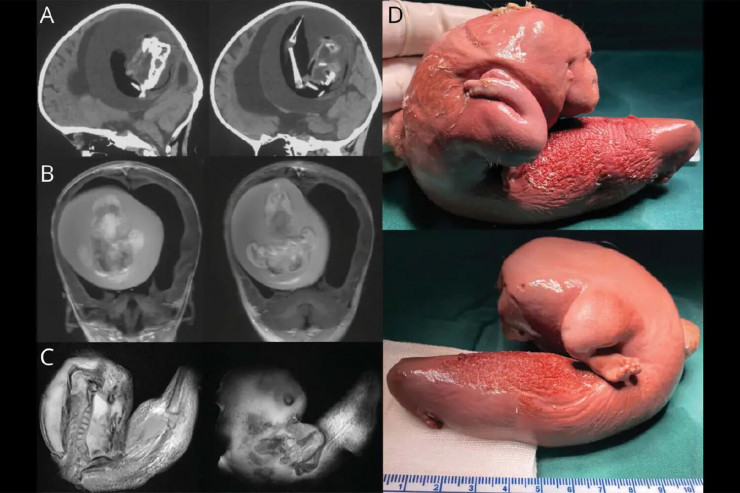

Ата-энеси кыздын баш сөөгү чоңоюп, кыймыл аракети начарлап жаткандыгынан ооруканага алып барганда кыздын мээсинде 10 сантиметрдей түйүлдүк табылган.

Дарыгерлер түйүлдүктүн үстүнкү буту, сөөктөрү, жада калса тырмактары өсүп калганын белгилешти. Демек, ал наристенин денесинде бир нече ай бою өсө берген. Бул түйүлдүктүн кан айлануу системасы кыздын кан айлануу системасына туташкандыктан мүмкүн болгон.

"Түйүлдүктөгү түйүлдүк" ("плод в плоде") - эгиздердин жатында биригип, бири экинчисинин ичинде физикалык жактан өнүккөн сейрек учурдун медициналык термини. Болгону 200гө жакын "түйүлдүктө түйүлдүк" фактысы катталган. Алар жамбашта, ооздон, ичегиден, табылган. Баш сөөк менен байланышкан 18 гана учур бар, алар көбүнчө ымыркайларда кездешет, бирок чоңдордо да бир нече учур катталган. Түйүлдүктү хирургиялык жол менен алып салгандан кийин бейтаптар, адатта, толугу менен айыгып кетет.